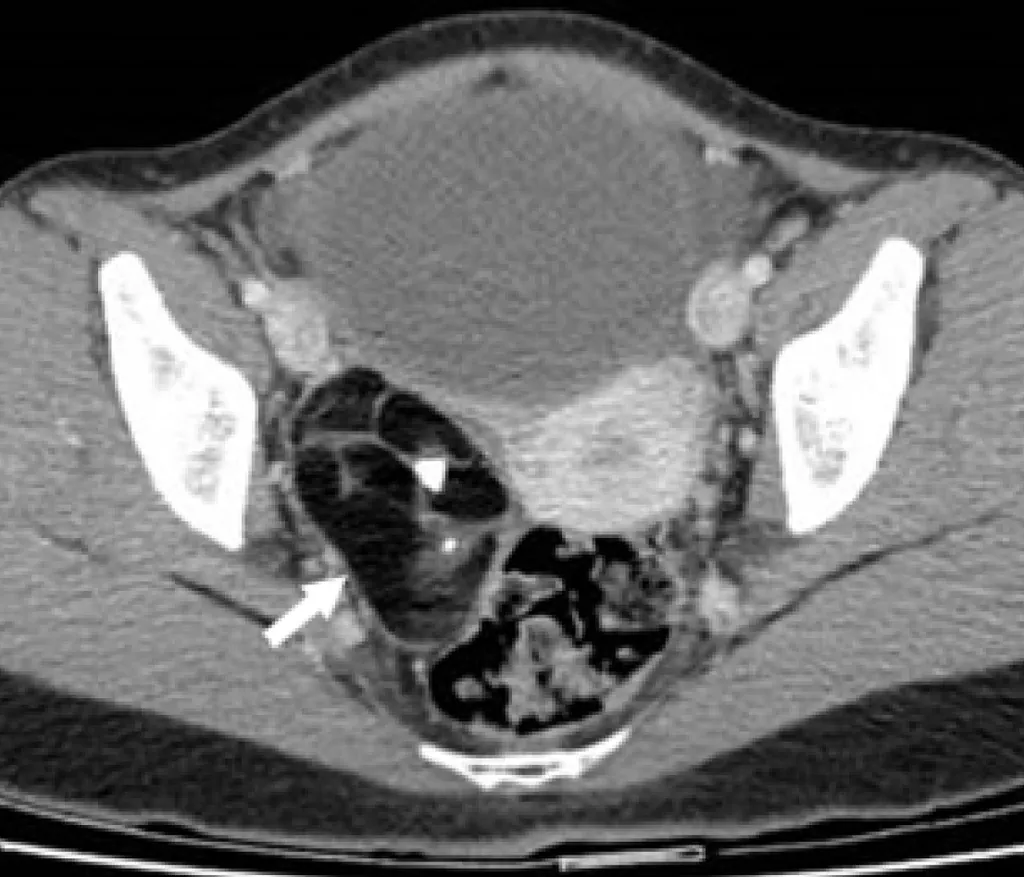

【115-1 醫學(五) 第73題】

35 歲女性病人主訴下腹疼痛,超音波檢查發現疑似右側卵巢腫塊,電腦斷層檢查呈現如圖,箭號所示最有可能的診斷為何?